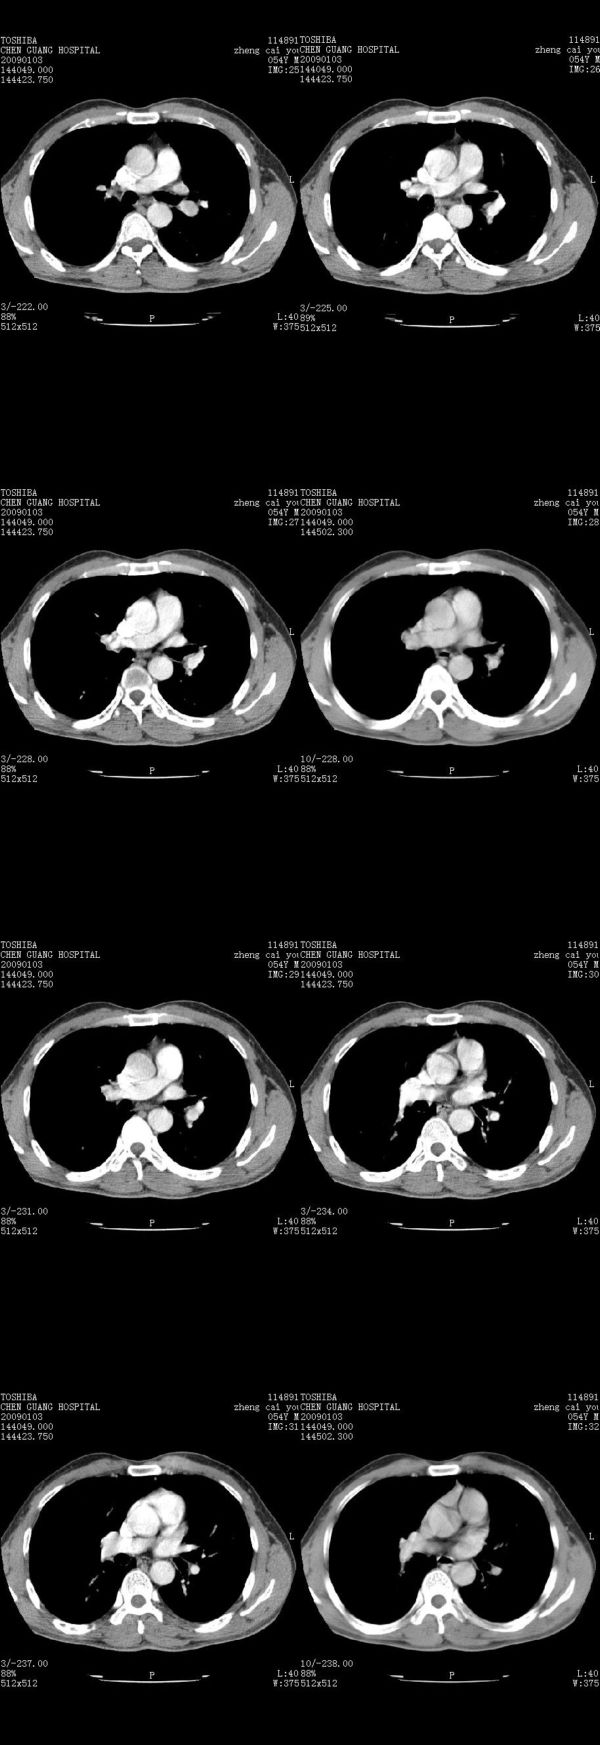

男,54岁,右侧胸部疼痛,平时吸烟,有抽烟后咳嗽咯痰史。昨天没把xiphoid软件吃懂,所以没把纵隔窗图像处理出来!请各位老师帮忙看一下右肺门有没有问题?谢谢!!!!!!!!!!

气管前腔静脉后似见增大淋巴结影,肺门区未见明显肿块影。肺窗示右肺中叶外侧段透亮度增高,可过一段时间再查一下对比一下,毕竟是自己的至亲,又有条件,辐射就顾不得了。

也觉得还好吧,只是右下肺动脉显粗了点,纵膈有钙化淋巴结,再有肺窗就更好了

各位老师:奇静脉增宽,肺上未见明显实变,这还需注意观察些什么?????

怎么不发点肺窗,胸痛原因很多,心、血管病变都可能,心、肺血管梗塞等,还包括功能性病变。

右侧肺门影增大,不除外增大淋巴结可能